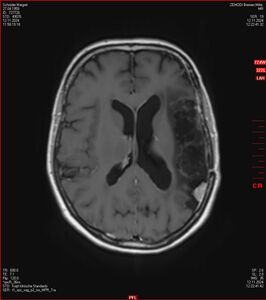

Die letzten drei Bilder Zeigen aus meiner Sicht den Tumor, der im Jahr 2021 bestrahlt wurde.

Ich denke, in den letzen 12 Monaten sind da ein paar Rezidive gewachsen,  vor 12 Monaten waren sie auch schon zu erkennen - vorher noch nicht. Nun hoffe ich auf den Rat des Spezialisten. Hoffendlich kann man etwas machen.